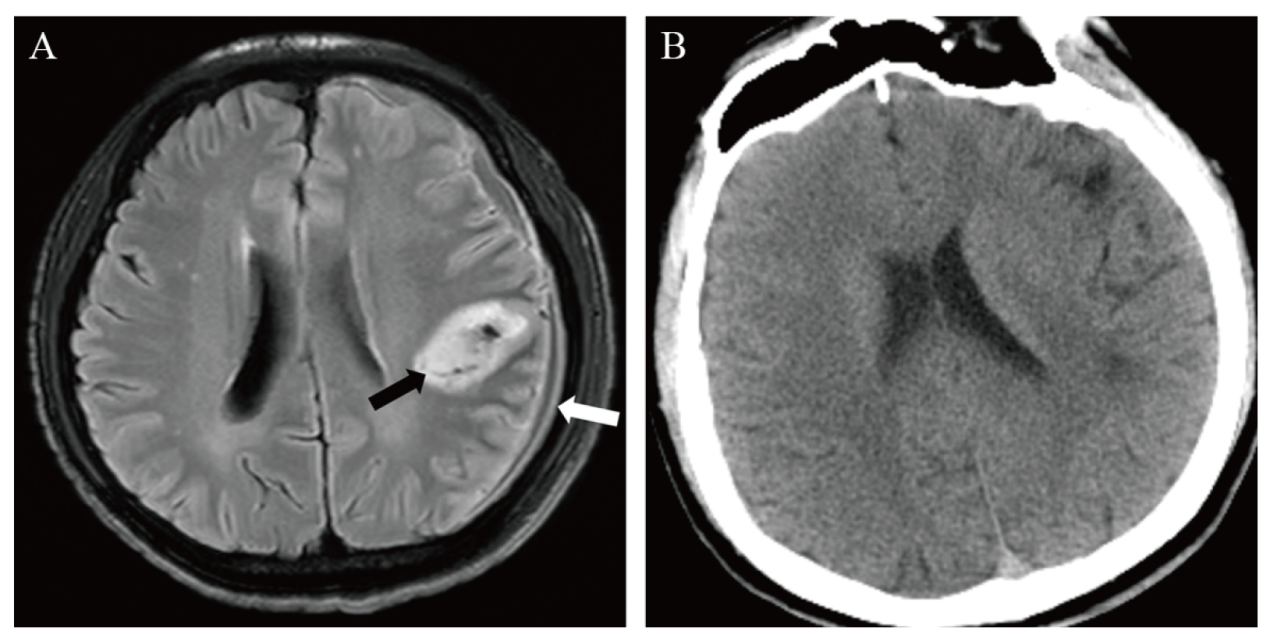

入院影像学检查:肺部CT提示双肺内多发斑片状影,考虑为肺部感染。颅脑CT提示左侧额顶部骨质内板下新月形稍低密度影,CT值约29 Hu,邻近脑实质受压、脑沟变浅,左侧侧脑室受压缩小,左侧额叶内结节状高密度影,周围未见水肿(图1A)。颅脑MRI提示左侧额顶部骨质内板下新月形异常信号影,其内可见液-液平面,其腹侧呈低T1加权像(T1WI)、高T2WI信号影,T2液体抑制反转恢复序列(FLAIR)呈低信号影,其背侧呈等T1WI、稍高T2WI信号影(图1BC),弥散加权成像(DWI)可见新月形异常信号背侧部分弥散受限(图1D),表观弥散系数(ADC)值约为774×10-6 mm2/s,增强扫描左侧额顶部硬脑膜明显强化,左侧额顶叶软脑膜轻度强化(图1EF)。

图1 一例艾滋病合并伤寒沙门菌感染致硬膜下脓肿患者入院影像学检查结果

注:检查时间为2020年9月22日。A为颅脑CT平扫,示左侧额顶部骨质内板下新月形稍低密度影(白箭头);B、C为颅脑MRI平扫T2WI及T1WI,示左侧额顶部骨质内板下新月形异常信号,其内可见液-液平面(白箭头);D为DWI,示新月形异常信号影背侧部分弥散受限;E、F为颅脑MRI T1WI增强矢状位及冠状位重建,示左侧额顶部硬脑膜明显强化(白箭头),左侧额顶叶软脑膜轻度强化(黑箭头)。